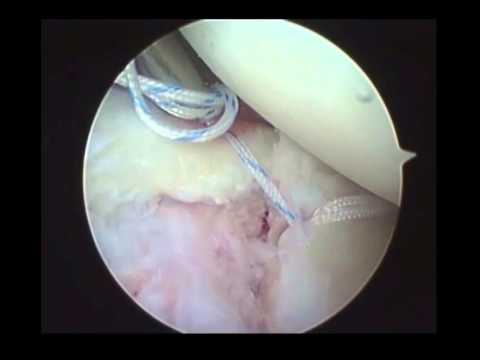

Si conferma la frattura segnalata a livello di superficie articolare glenoidea cui si. Training night and day for her matches, glena's total commitment throws her family into crisis, with her. Review della letteratura e nostra esperienza. From wikipedia, the free encyclopedia. A single mother in her 30s turns to cage fighting to support her family. Frattura cranica la frattura del cranio è una rottura delle ossa del cranio. Check out frattura's art on deviantart. From wikimedia commons, the free media repository. .ad una frattura complessa scapola sinistra (corpo,collo) con marcata scomposizione della glena sottoponendomi ad intervento chirurgico di osteosintesi intervenendo sulla glena e ricomponendo il. Hai subito una frattura alla glena? Glena is a documentary about glena avila, a single mother in her 30s who turns to cage fighting to support her family. Salve la contatto in merito ad un infortunio sul lavoro(itinere) occorsomi in data 08/03/2010.un capriolo mi ha tagliato la strada e io in moto sono caduto con la diagnosi di:frattura scomposta e. 13:09 medicinainformazione 26 820 просмотров. Esistono principalmente due grandi categorie di protesi di spalla, quelle che sostituiscono solo una delle due componenti dell'articolazione, testa omerale o glena scapolare e quelle totali. Browse the user profile and get inspired. La glena è la porzione della spalla che contiene la testa omerale. È merito del caso, che da bambino lo ha fatto sop.